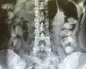

به گزارش مخاطب ۲۴ به نقل از سازمان تامین اجتماعی ؛دکتر غلامحسین پورآذر متخصص جراحی عمومی بیمارستان فاطمه الزهرا (س) نجف‌آباد اصفهان و سرپرست تیم انجام‌دهنده یکی از این جراحی‌ها گفت: خانمی ۴۱ ساله که در حین کار در کارگاه تولیدی، دست راست وی به شدت آسیب دیده بود به این بیمارستان منتقل شد. بعد از انتقال بیمار به بیمارستان، دست این بیمار با تلاش ۵ ساعته گروه ۱۰ نفره پزشکان این بیمارستان با موفقیت پیوند زده شد. این بیمار که در کارخانه ریسندگی دچار حادثه و از ناحیه آرنج و ساعد دست راست، شدیداً دچار پارگی و له شدگی مفصل و استخوان‌ها شده بود، در اتاق عمل این مرکز، جراحی شد که نتیجه این جراحی رضایت‌بخش بوده و شرایط دست بیمار رو به بهبود است.

وی ادامه داد: عملیات احیای اولیه با دریافت خون، مایعات و دارو‌های بیهوشی برای ایشان صورت گرفت و عملیات بازسازی عروق انجام شد. بعد از جراحی، بلافاصله کار‌های ارتوپدی شروع شد. ترمیم عصب، تاندون‌ها، عضلات و استخوان‌ها در سریعترین زمان ممکن انجام گرفت و بیمار در حال حاضر اندام زنده و سالمی دارد و حس و حرکت دست هم قابل قبول است.

اعظم س. بیمار ۴۱ ساله که به تازگی در بیمارستان فاطمه‌الزهرا (س) نجف‌آباد تحت جراحی پیوند عروق دست قرار گرفته است نیز در مورد این حادثه گفت: بعد از اتمام کار روزانه، درحالی‌که مشغول خاموش کردن دستگاه بودم، دستم بین نمد و غلطک دستگاه درگیر شد و از ناحیه مچ تا آرنج آسیب شدید دید و استخوان این قسمت به ۶ تکه تقسیم شد.

وی گفت: با تلاش پزشکان حاذق و تیم جراحی بیمارستان نجف‌آباد با تزریق ۳ واحد خون و ۱۱ واحد پلاکت و پیوند عروق و رگ، دستم از شرایط بافت مرده خارج شد و خوشبختانه منجر به قطع شدن نشد. در حال حاضر چند روزی است که عمل کرده‌ام. محدودیت حرکتی دارم، اما کار‌های روزانه‌ام را شخصاً و بدون کمک گرفتن از دیگران انجام می‌دهم.